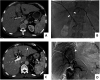

Methods: Forty advanced eCCA patients who received percutaneous transhepatic biliary stenting (PTBS) (control group) and 40 PTBS combined with 125I seed implantation (125I group) were retrospectively analyzed. Changes in serum biochemical indicators and tumor markers as well as the occurrence of complications were observed in the two groups, and the durations of stent patency and survival were compared.

Results: The general information and preoperative baseline data did not significantly differ between the two groups (P < 0.05). Regardless of whether PTBS was combined with 125I seed implantation, the ALT/AST levels of patients after operation were significantly lower, jaundice was relieved. And the improvements in postoperative liver function and jaundice in patients in 125I group were better than those in control group. In addition, tumor markers in the two groups decreased significantly, and the decrease was more significant in patients in 125I group. There was no significant difference in the total complication rate between the two groups. The stent patency time and overall survival of the patients in the 125I group were longer than those in control group.

Conclusion: Biliary stenting combined with 125I seed implantation is a safe and effective treatment for patients with advanced eCCA, and it is superior to biliary stenting alone in improving liver function and prolonging the duration of stent patency and survival time.